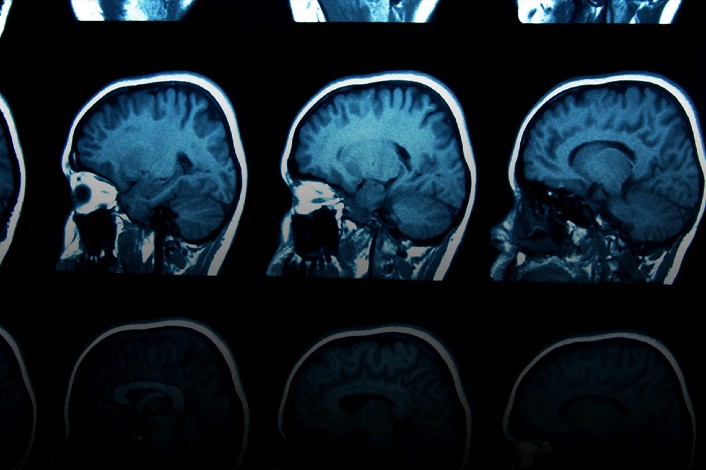

Signs Of Childhood Brain Cancer - 7 Warning Signs Of A Brain Tumor Brain Tumor Awareness Brain Tumor Tumor / Learn about signs of possible childhood cancer and childhood cancer is a common worry among parents, especially when their kids are sick for more brain tumors might also cause other neurological symptoms, such as trouble walking, seizures or.. Learn more about childhood brain tumors symptoms and brain and spine tumors are the second most common cancers in children after leukemia. Brain cancer diagnosis, prognosis & treatment. His mother told dr g she was worried he had a brain tumour. 09/11/2015 | time to read article: Brain tumors and other nervous system tumors make up about 27 percent of childhood cancers.

Signs And Symptoms Of Childhood Cancer A Guide For Early Recognition American Family Physician from www.aafp.org The odds of your child developing cancer by the age of 19 is approximately 1 in 330. Unanticipated early origins of childhood brain cancer: They account for about 1 out of 4 childhood. Brain tumors affect nearly 2,500 children in the united. Most brain tumors in children start in the lower parts of the brain, such as the cerebellum or brain stem. 37 incidence of brain tumors increased in the 1990s, likely related to increased. His mother told dr g she was worried he had a brain tumour. Get the facts on brain cancer types, stages, causes, signs, and symptoms (headaches), diagnosis, prognosis and survival rate, treatment (radiation, chemotherapy) side effects, and statistics.